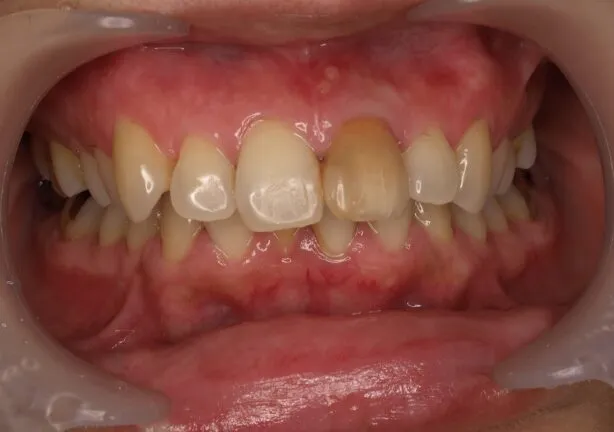

case2

Before

After

治療内容 | 口腔内診査〜カウンセリング 歯周初期治療 仮歯にて噛む位置の再設定 インプラント埋入 仮歯にてインプラントを含めた噛む位置の決定 最終的な被せ物(ジルコニア)の型取り〜装着 |

---|---|

治療期間 | 1年半 |

治療回数 | 40回 |

リスク | リーニングにこない場合噛み合わせの確認ができないため装着していった人工物が割れてしまう可能性があるため、今後のメンテナンスが必須となる |

費用(税込) | 約¥2,860,000 |